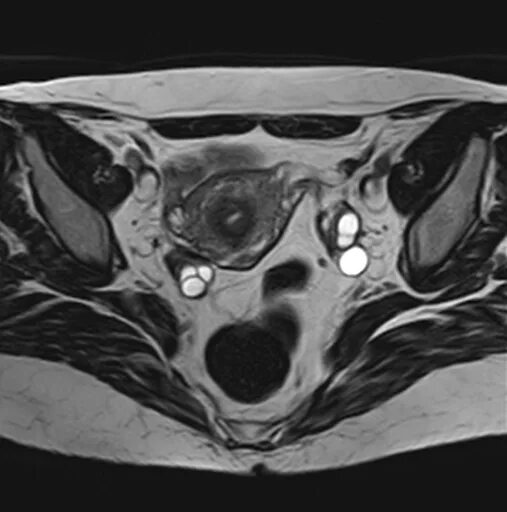

Аденомиоз диффузные изменения